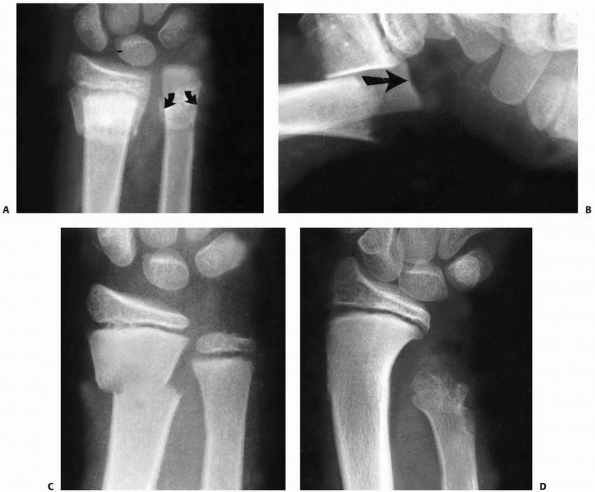

![]() |

|

FIGURE 9-10 A.

Subperiosteal hemorrhage from an occult fracture of the distal radius causes an anterior displacement of the normal pronator quadratus fat pad (arrows). B. A 13-year-old girl with tenderness over the distal radius after a fall. The only radiographic finding is an anterior displacement of the normal pronator quadratus fat pad (arrow). C. The opposite normal side (arrow indicates normal fat pad). D. Two weeks later, there is a small area of periosteal new bone formation (arrow) anteriorly, substantiating that bony injury has occurred. |